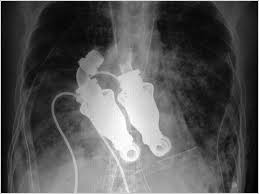

Jakub Halik vive con ayuda de dos bombas sin válvulas cardiacas. (Reuters)

Jakub Halik vive sin corazón  desde hace cinco meses, conectado a dos bombas sin válvulas cardíacas, pero apenas se da cuenta de ello. Este bombero de 37 años se ha convertido en la primera persona en sobrevivir en una operación de este tipo, que le ha permitido poder vivir cinco meses sin corazón.

Esta intervención consiste en instalar dos bombas Heartmate II para realizar el bombeo de la sangre a todo el cuerpo, por un lado, y a los pulmones, por otro.